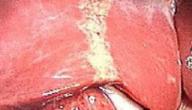

تعني دهون الكبد بأنّ هناك زيادةً في كمية الدهون المتراكمة في تجاويف الكبد ممّا يٌعيق عملها ويبطئه، الأمر الذي يؤشر إلى حالةٍ مرضيةٍ خطيرةٍ على صحة الإنسان تبدأ بتليّف الكبد وتنتهي بتشمّع الكبد، وقد يتطور المرض إلى التسبب بإصابة الكبد بالسرطان، كما تتسبب هذه الدهون بارتفاعٍ في نسبة الأنزيمات التي يفرزها الكبد مما ينتج عنها ارتفاع في مستوى الحديد في الدم.

تختلف مضاعفات تراكم الدهون في الكبد من شخصٍ إلى آخر؛ فالبعض تنتج لديه التهاباتٌ في الكبد تؤدي إلى توّقف عمل الكبد بالتدريج حتى تفقد قدرتها على العمل، فيفقد الجسم عضواً مهماً فيه، والبعض الآخر ينتج عنده تشمّعٌ وتليّفٌ في الكبد يتوقف عمله أيضاً، مما يتسبب بالوفاة.